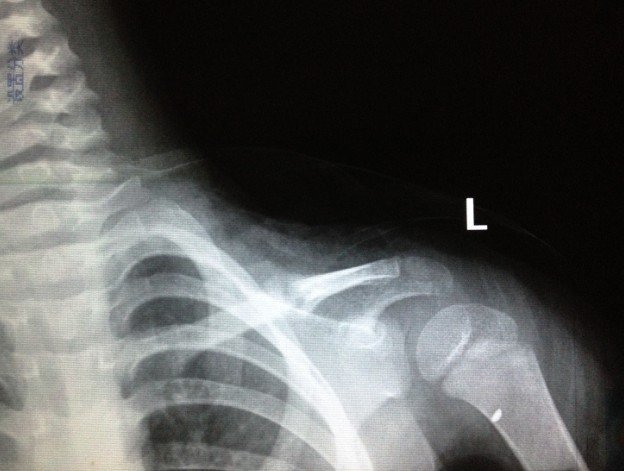

宝宝3岁半出车祸左锁骨骨折

2012.10.7日发送车祸,X片确诊为左锁骨骨折。现在已经自行把八字绷带取下,请问这样做可以吗?因为孩子的腋下已经开始有轻微溃烂的症状(掉干壳壳)前段时间因为出车祸导致孩子的左锁骨骨折,去医院打了八字绷带,刚好一个月去医院复查,医生说已经开始长骨痂,建议继续八字绷带半个月,今天宝宝一直吵着说腋下痛,我才发现宝宝的腋下有那种干裂的壳状的掉出,而且腋下非常的红。孩子的奶奶处于心痛孩子,就把绷带给取了,请问这样做妥当吗?会影响孩子骨折的生长吗?如可以取下,家长应该注意些什么细节呢?谢谢!“下面的X光片拍摄于2012年11月3日”